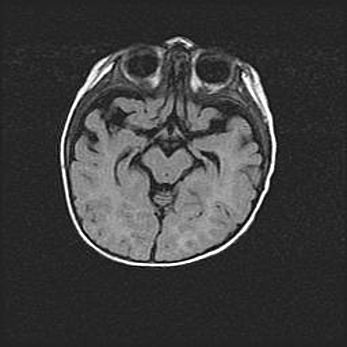

Наружная гидроцефалия с возможной атрофией височных областей.

Возраст: 28 дней

Вес: 3670 г

Пол: мужской

Окружность головы: 38 см

Срок гестации: 40 недель

Гидроцефалия головного мозга у новорожденных – это заболевание, которое характеризуется скоплением избыточного количества спинномозговой жидкости в желудочковой системе головного мозга в результате затруднения её перемещения от места выработки к месту поглощения в кровеносную систему или вследствие нарушения абсорбции. При открытой наружной форме гидроцефалии у новорожденных расширяются и переполняются субарахноидные пространства.

При нормотензивных  формах,  которые,  как  правило,  являются  следствием  перенесенных ишемических  повреждений  паренхимы  мозга,  возможно  сочетание микроцефалии  с нормотензивной гидроцефалией. В основе данных изменений лежит атрофия больших полушарий с преимущественной  локализацией  в  лобно-височных  областях.